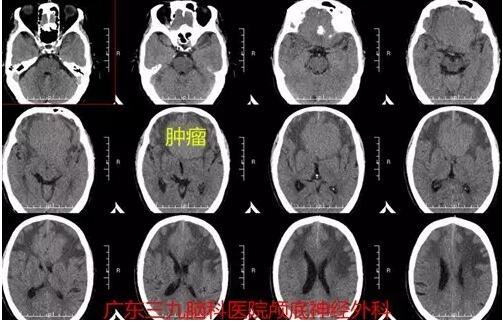

黄先生今年64岁,1个月前他开始出现头痛、头晕的症状。在家属的陪伴下,他于近日来到广东三九脑科医院神经外科就诊,影像结果显示前颅窝底占位性病变,考虑前颅窝底脑膜瘤。

据神经外一科主任张良介绍,嗅沟脑膜瘤起源于前颅底筛骨筛板处的硬膜,因为肿瘤位于前颅窝底,额叶在功能上属于“哑区”,主要症状可有颅内压增高症状、视力减退、癫痫以及精神症状等。头痛原因较复杂,可能为肿瘤对硬脑膜的刺激所致,为颅高压导致头痛时,肿瘤常已较大。大部分患者就诊发现肿瘤时瘤体多已巨大,瘤体双侧生长,以头晕头痛的颅内压增高症状起病,黄先生发病时检查肿瘤体积已达5.9×6.3×3.5cm。

图1: 术前CT显示肿瘤前颅窝底一巨大团块状占位性病变,呈等密度,中有钙化,周围水肿带